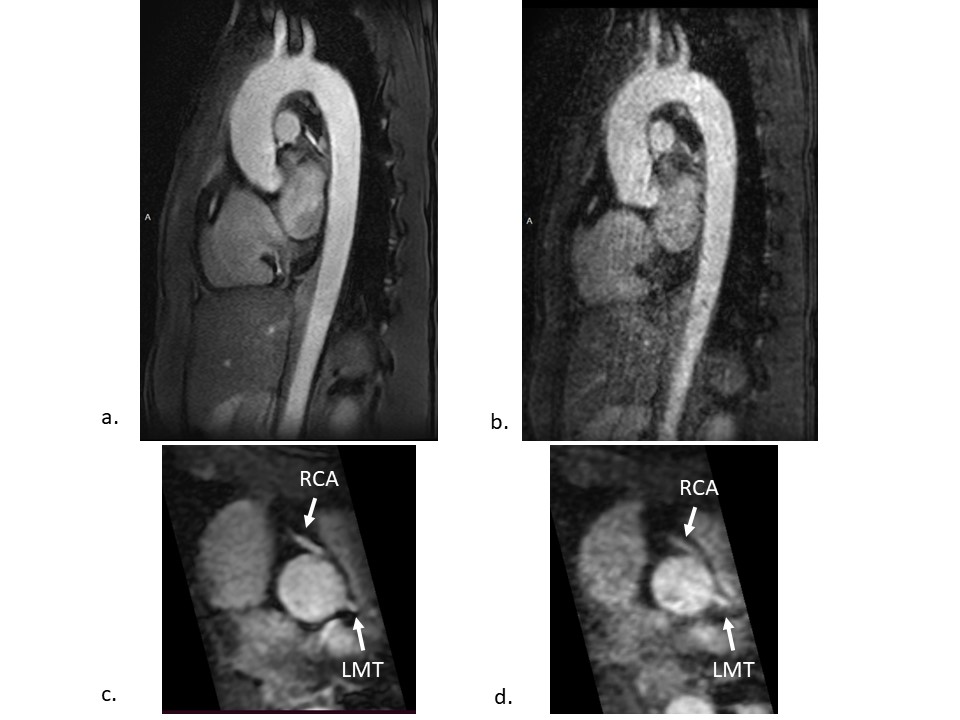

Figure 3 shows typical sagittal oblique TA images and multiplanar reformatted images at the level of the sinus of Valsalva of 3D centric ky-kz FFE with HR-DLR and conventional FFE. The 3D centric ky-kz FFE with HR-DLR offers high-resolution images without sacrificing signal intensity and contrast with a scan time of less than 60 seconds. The sharpness of vessel structures is obtained with HR-DLR. On the other hand, conventional FFE images scanned within 90 seconds are suffered from phase-encoded motion artifacts and noises. Image quality was higher in the proposed method than in the conventional method (mean, 4.0 vs. 2.4, p<0.05).

3D centric ky-kz fast field echo (FFE) images with high-resolution deep learning reconstruction (a, c) and conventional FFE images (b, d). Sagittal oblique images (a, b) and multiplanar reconstruction images at the level of the sinus of Valsalva (c, d). LMT = left main trunk, RCA = right coronary artery.